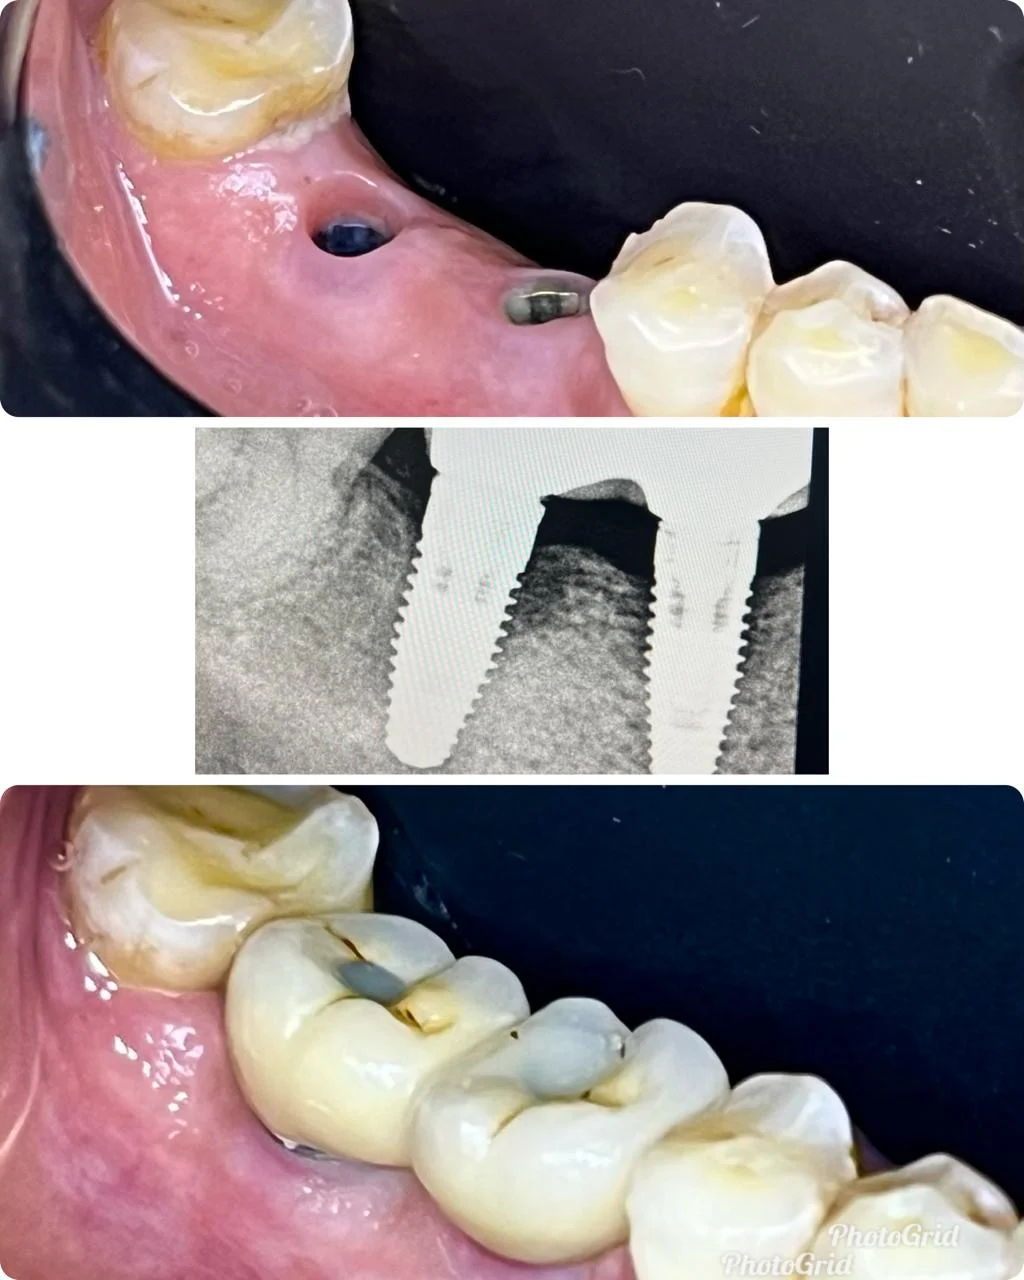

Showing Our Expertise In Dental Implantology